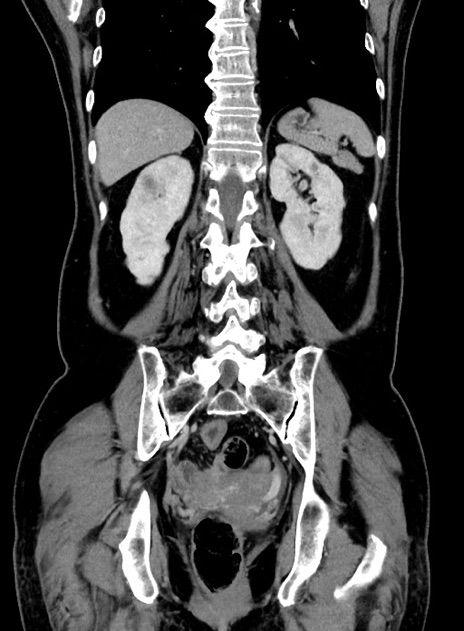

症例9(冠状断像)

【症例】 60歳代女性

【主訴】むかつき、みぞおちの痛み

【現病歴】3日前よりむかつきがあり、食事がとれない。

【既往歴】糖尿病

【身体所見】発熱なし、心窩部圧痛軽度あるも、腹膜刺激症状なし。

【データ】WBC 7400、CRP 1.92